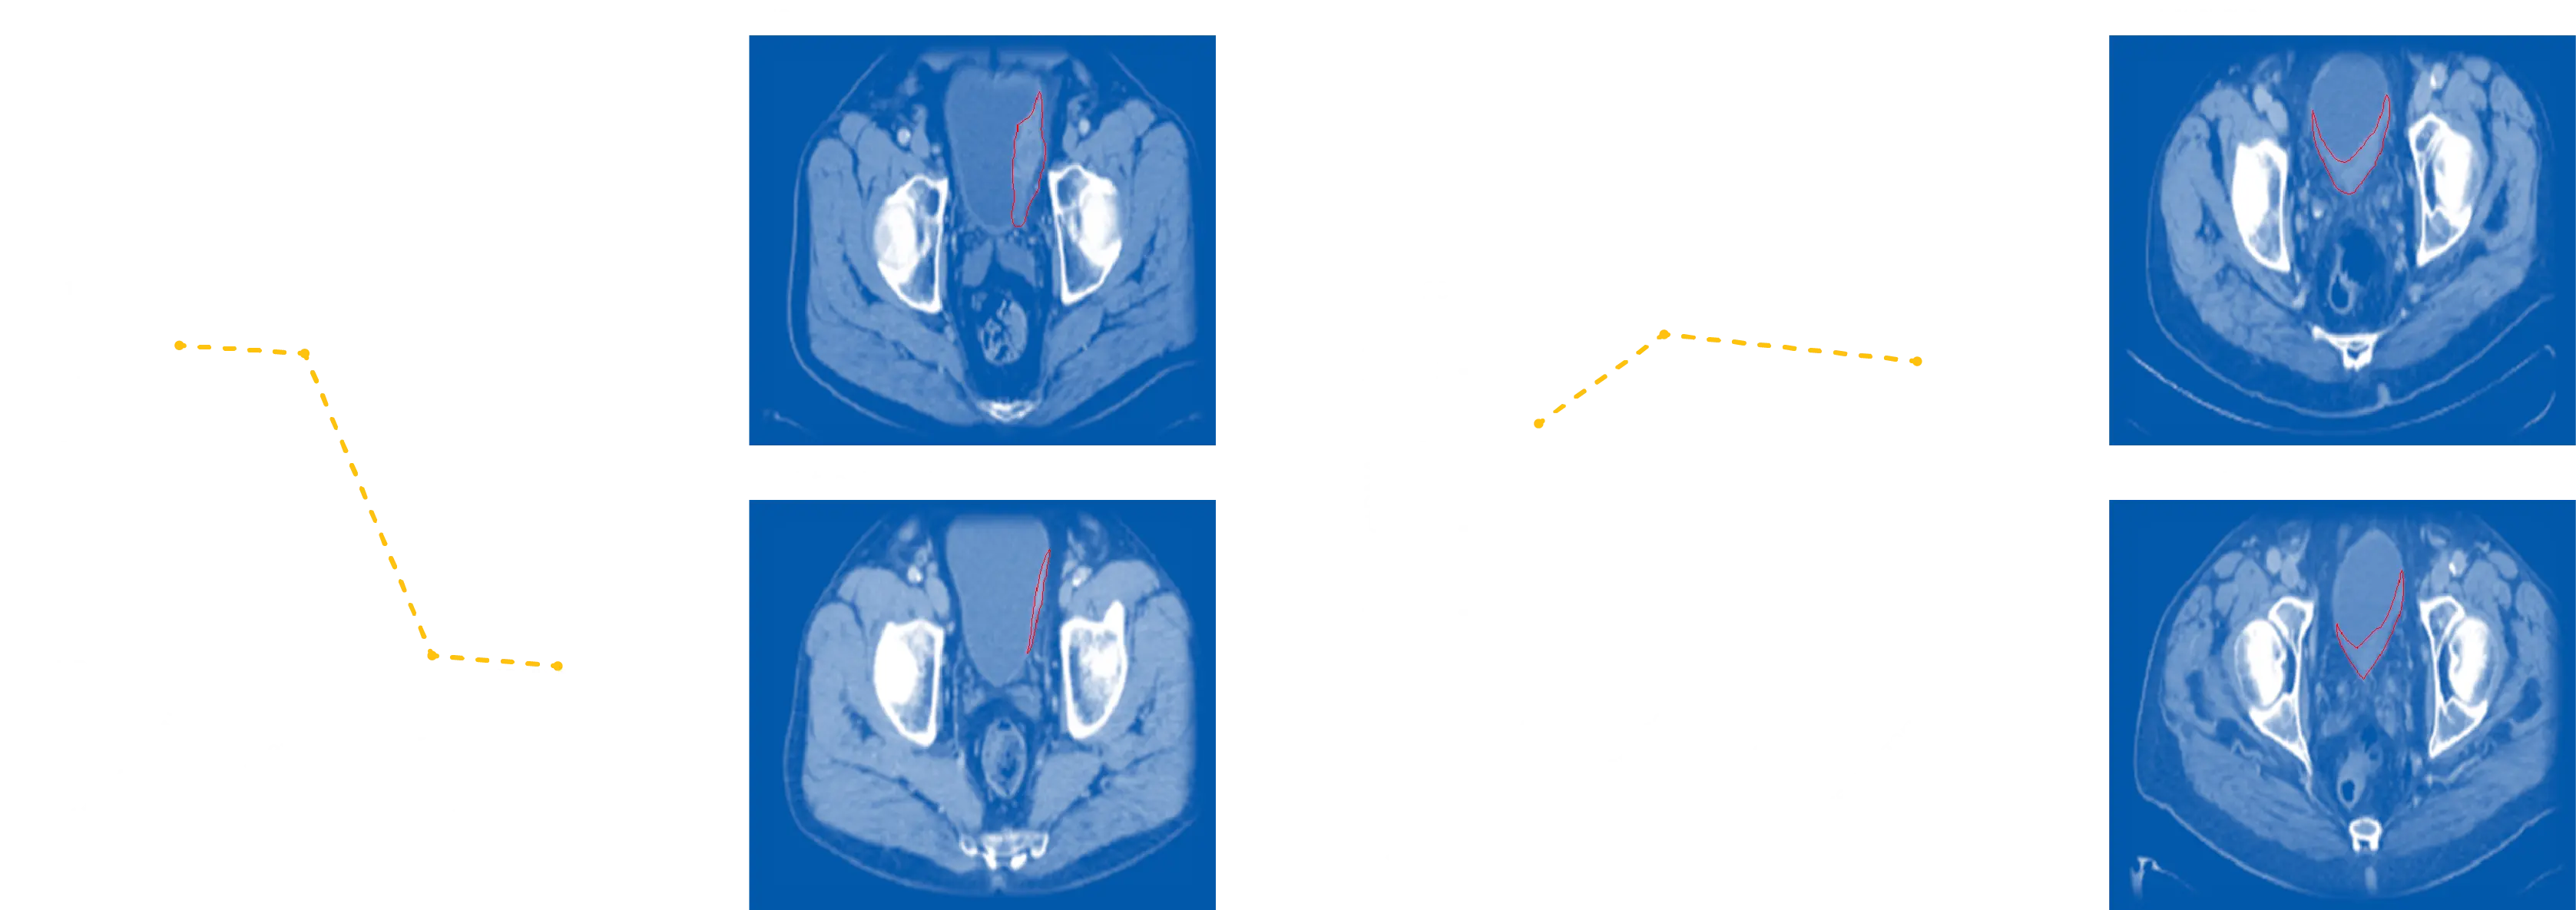

RaDaR ST utilizes whole exome sequencing (WES) data from tumor samples and bioinformatic pipelines to develop bespoke MRD panels. The RaDaR ST approach leverages high-depth sequencing with personalized panels to achieve highly sensitive and specific ctDNA detection from plasma samples.